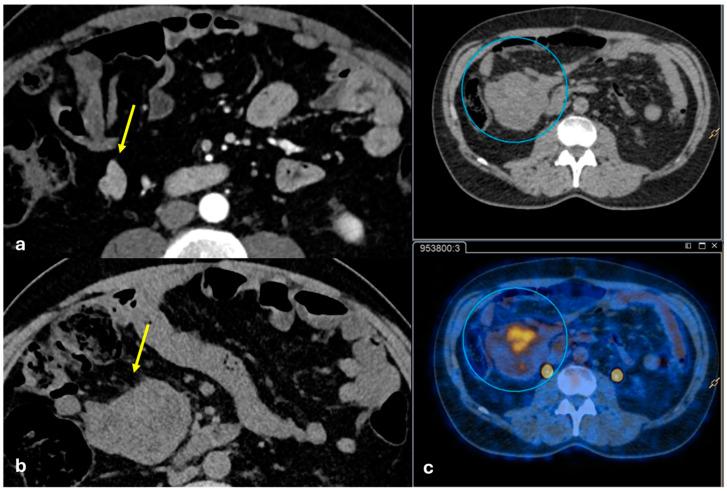

The peritoneum is a thin membrane that lines the abdominal cavity and covers the abdominal organs. It serves as a conduit for the spread of various pathological processes, including gas and fluid collections, inflammation, infections, and neoplastic conditions. Peritoneal carcinomatosis is the most common and well-known pathology involving the peritoneum, typically resulting from the dissemination of gastrointestinal and pelvic malignancies. However, numerous benign and malignant peritoneal diseases can mimic the imaging appearance of peritoneal carcinomatosis. The aim of this review is to revisit the anatomy of peritoneal compartments and elucidate the patterns of peritoneal disease spread. Emphasis is placed on identifying the distinctive imaging features of both neoplastic and non-neoplastic peritoneal diseases that differ from peritoneal carcinomatosis.

腹膜是一层薄的膜,它衬于腹腔内并覆盖腹部器官。它是各种病理过程扩散的通道,包括气体和液体聚集、炎症、感染及肿瘤性疾病。腹膜癌病是涉及腹膜的最常见且广为人知的病理情况,通常由胃肠道和盆腔恶性肿瘤的播散引起。然而,许多良性和恶性腹膜疾病可模仿腹膜癌病的影像学表现。本综述的目的是重新审视腹膜腔室的解剖结构并阐明腹膜疾病的扩散模式。重点在于识别与腹膜癌病不同的肿瘤性和非肿瘤性腹膜疾病的独特影像学特征。